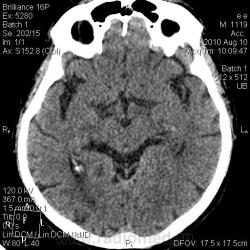

От 10.08.10 г.: В лобной доле левого полушария головного мозга кнаружи от переднего рога левого бокового желудочка гиподенсивная зона неправильной формы. В остальном картина соответствует возрасту. От 13.08.10 г.: на мой взгляд, плотность указанной зоны ещё уменьшилась и появился гиподесивный учаток в височной доле левого же полушария. Заключение: КТ-картина ишемических инфарктов в левом полушарии головного мозга различной степени давности.

Спасибо dok-a и Сергею Николаевичу за мнения. Я выставила ишемический инсульт. Первый раз, когда пациент (кстати, врач) пришел сам, была легкая оглушенность. Второй раз привезли на каталке, галлюциноз. За несколько дней консультирован и нашими, и областными неврологами. Не укладывалась клиника только в инсульт. Ликвор, взятый у нас - без особенностей. Мне показалась не совсем нормальной картина для инсульта на КТ. Но для постановки диагноза интуиции мало. Через 3 дня после поступления фербильная t. Кашель, сухие и влажные хрипы. В легких застойные дела. На КТ-контроле появилась зона ишемии в базальных отделах левой височной доли (предрекаемая неврологами по клинике и невидимая на первичной КТ). Переведен в область уже с судорогами. Через 2 недели возвращен к нам с верифицированным диагнозом ГЕРПЕТИЧЕСКОГО ЭНЦЕФАЛИТА. Учитывая редкость заболевания, выставляю здесь.